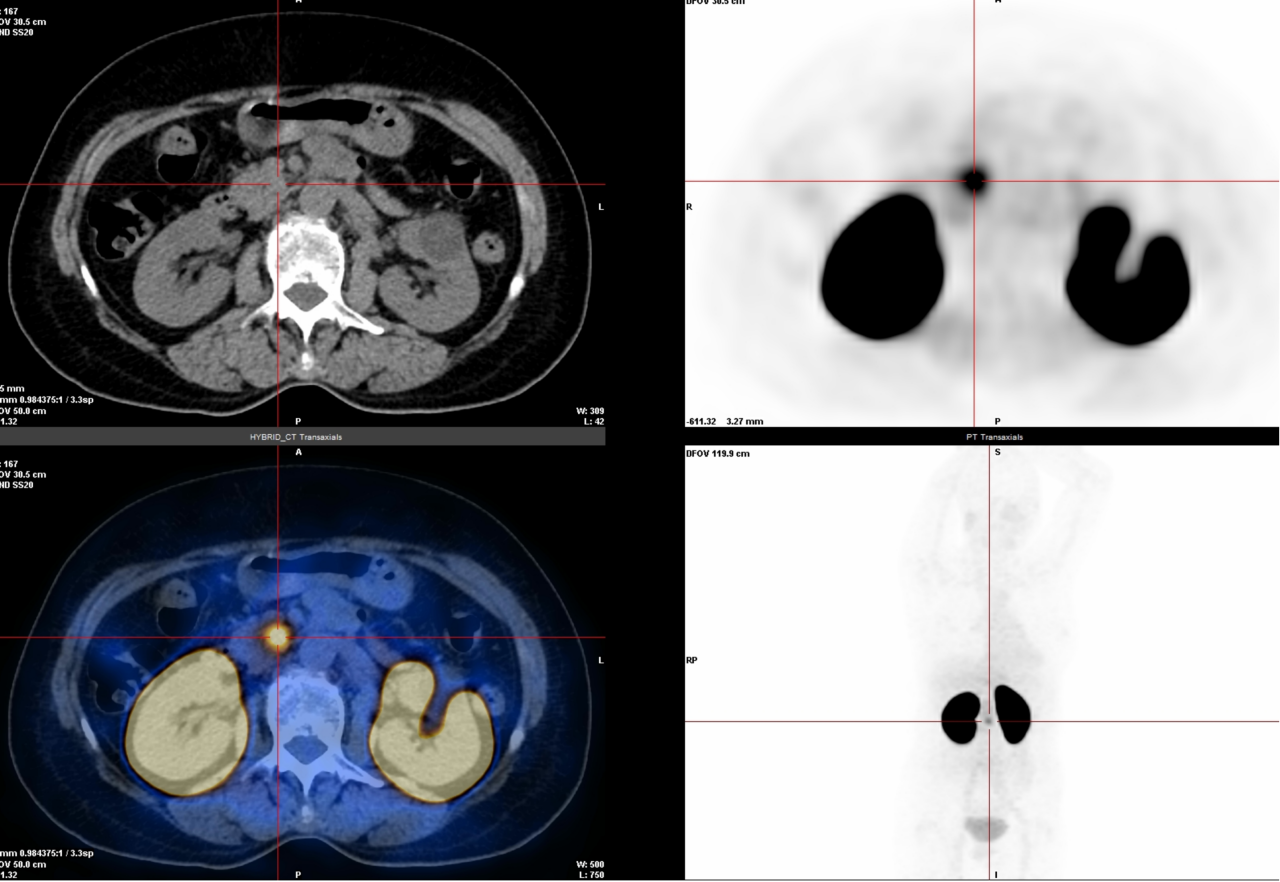

△腹膜转移癌

3.神经内分泌肿瘤检查(68Ga-DOTATATE):专门针对神经内分泌肿瘤(比如某些胃肠胰肿瘤、类癌等),能准确找到肿瘤位置,判断严重程度和治疗效果。

△神经内分泌癌骨骼多发转移